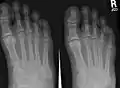

X-ray of foot, showing phalangeal fracture